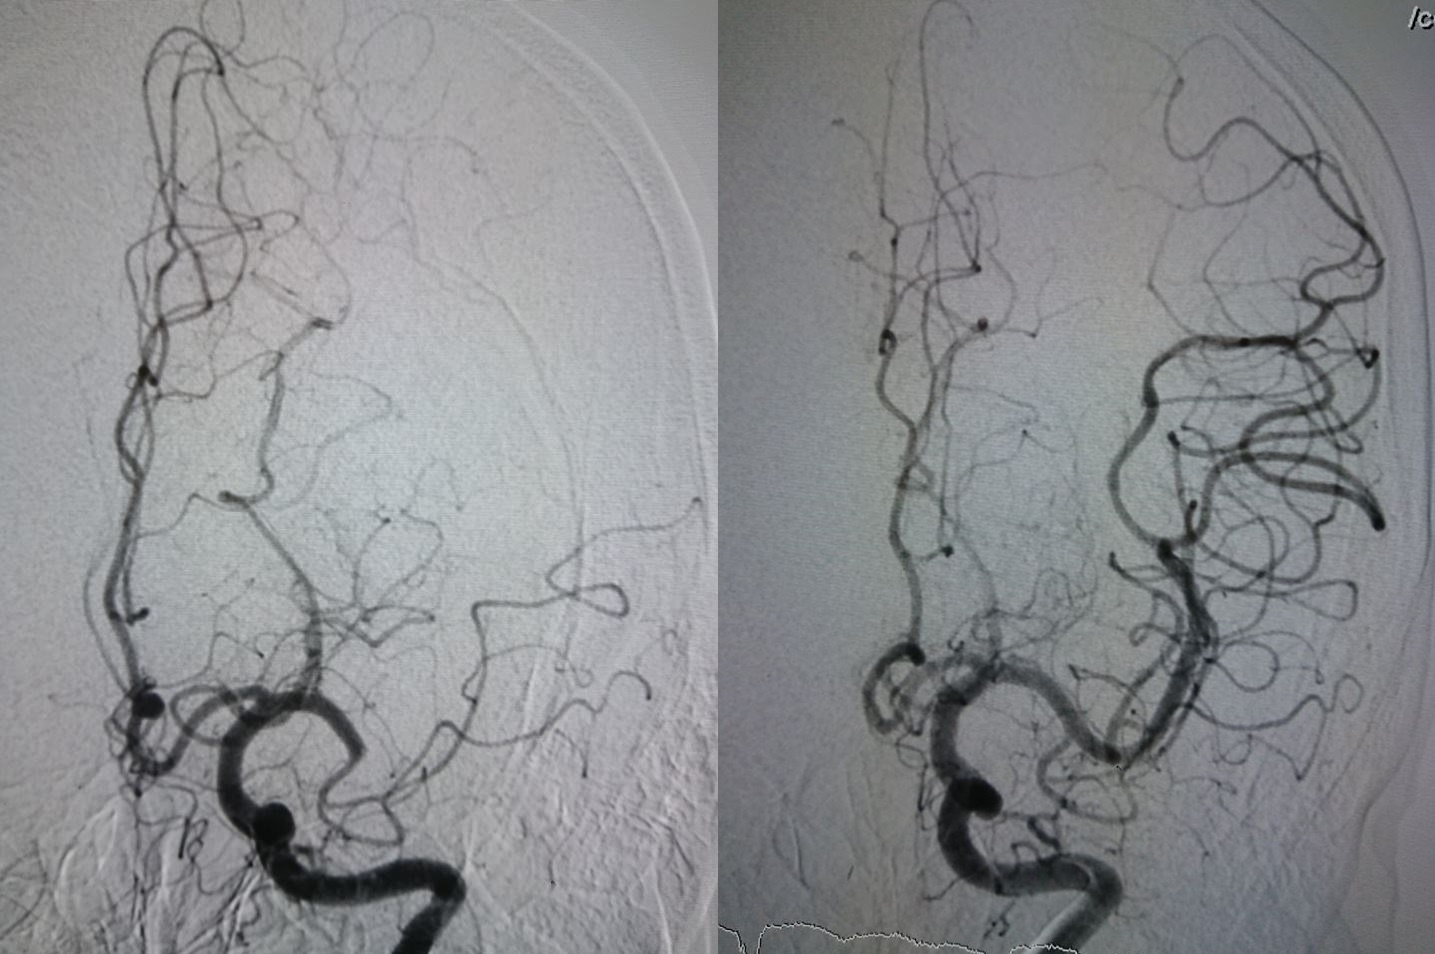

Các bác sĩ sau đó đã nhanh chóng hội chẩn, quyết định sử dụng kỹ thuật can thiệp lấy huyết khối nội mạch để điều trị cho bệnh nhân. BSCKII Ông Văn Mỹ, BSCKI Trần Công Khánh cùng ê-kíp bệnh viện đã thực hiện cuộc phẫu thuật. Sau 30 phút can thiệp, bệnh nhân được tái thông tuần hoàn não.

| Hình ảnh trước và sau khi tái thông động mạch tắc. Ảnh: BVCC. |

BSCKII Ông Văn Mỹ, Phó trưởng khoa Hồi sức tích cực - Chống độc, Phó trưởng Phân khoa Can thiệp mạch não, cho biết bệnh nhân đột quỵ não do tắc động mạch não giữa nếu không điều trị kịp thời có tỷ lệ tử vong 90%. Trường hợp còn sống có thể để lại di chứng nặng nề là yếu hoặc liệt nửa người.